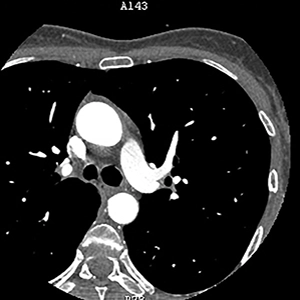

CT calcium scoring, also may be called a coronary calcium scan or heart scan, is a specialized X-ray scan used as a routine screening for early detection of calcium-containing plaque in the arteries. Calcium build up in the coronary arteries affects the level of blood and oxygen delivered to the heart, a key risk factor for heart disease. As calcium builds up in the arteries, they can begin to narrow or become blocked. The narrowing or blockage can result in symptoms such as chest pain, shortness of breath, and/or fatigue.

Getting a CT calcium score is quick, non-invasive and typically takes less than 15 minutes. Prior to the scan, an electrocardiograph (ECG) machine will have electrodes, or tiny metal discs, placed on your chest to ensure the CT is able to capture images when the heart is not actively contracting. You’ll lie still on a table while the CT scanner, featuring an open back for comfort, captures high-resolution images of your heart. There’s no need to change clothes, and you won’t be given any contrast dye via an IV. Throughout the scan, you will be in steady communication with a trained technologist who will guide you through each step to make sure you are at ease.

After your scan, one of our board-certified radiologists will evaluate the images and detail the amount of calcium plaque in each of your heart’s arteries. The results are scored numerically to indicate your risk level for heart disease.